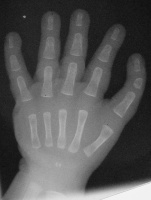

| Left hand: |

| Immediately preop. |

| The same type of procedure was performed on both hands at the same setting. This included a shortening/straightening proximal interphalangeal joint fusion and a shortening/pronating/abducting metacarpal osteotomy, along with extensor tendon shortening. Bone fixation at each site was with an intramedullary absorbable pin and intraosseous PDS sutures. Red areas are the areas of skeletal removal. |